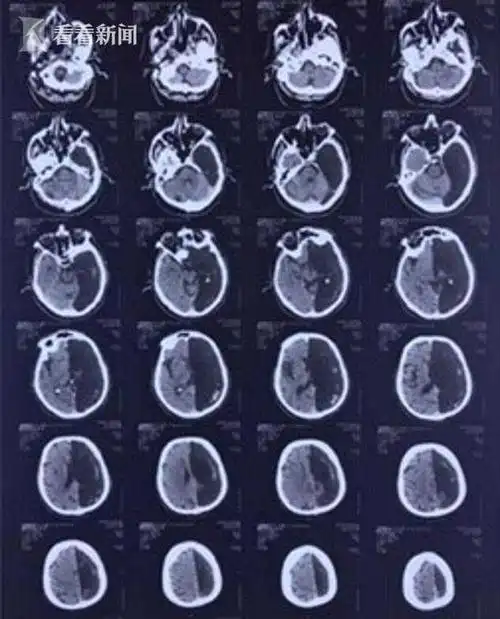

图-24:2020年1月22日头颅核磁图-25:2020年1月29日头颅ct图-26:2020年